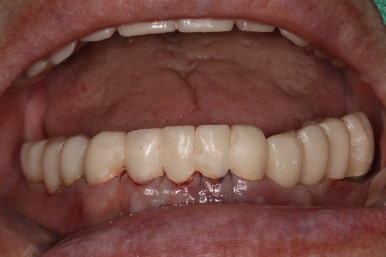

그렇게 완성된 최종 보철물 형태입니다.

임시치아와 다르게 지르코니아 크라운으로 제작되어 훨씬 단단하고 매끈하고 이상적인 형태를 가진걸 보실 수 있으실거에요.

위 아래 앞니 모두 적절한 길이로 회복이 되었고, 어금니도 이상적인 형태를 보여주고 있습니다.

제거가 덜 된 접착제가 조금 보이긴 하지만,

좌우로 옆에서 봤을 때도 충분히 기능이 잘 되게끔 잘 물리는 어금니를 보실 수 있을거에요.

식사 시 음식이 덜 끼도록 치아와 치아사이를 최대한 닫아놓은 모양입니다.

위아래 모두 아주 이상적인 형태로 제작된 치아모양의 지르코니아 크라운을 보실 수 있을거에요.

이 정도면 전체 구강 재건 (full arch rehabilitation)이라고 불러야 합니다.

Before & After!!

솔직히 제가 봐도 미라클한 최종 치료 사진...

적절한 색조와 형태를 가진 앞니 보철물.. 그리고 적절히 기능하도록 설정된 아래턱의 위치

모든것이 조화롭게 완성된 치료 후 구강내 사진입니다.

환자분도 정말 너무너무 대만족 하셨어요 :)